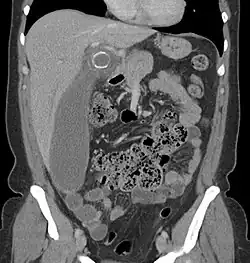

A CT scan demonstrating acute appendicitis (note the appendix has a diameter of 17.1 mm and there is surrounding fat stranding).

The accurate diagnosis of appendicitis is multi-tiered, with the size of the appendix having the strongest positive predictive value, while indirect features can either increase or decrease sensitivity and specificity. A size of over 6 mm is both 95% sensitive and specific for appendicitis.[66]

However, because the appendix can be filled with fecal material, causing intraluminal distention, this criterion has shown limited utility in more recent meta-analyses.[67] This is as opposed to ultrasound, in which the wall of the appendix can be more easily distinguished from intraluminal feces. In such scenarios, ancillary features such as increased wall enhancement as compared to adjacent bowel and inflammation of the surrounding fat, or fat stranding, can be supportive of the diagnosis. However, their absence does not preclude it. In severe cases with perforation, an adjacent phlegmon or abscess can be seen. Dense fluid layering in the pelvis can also result, related to either pus or enteric spillage. When patients are thin or younger, the relative absence of fat can make the appendix and surrounding fat stranding difficult to see.[67]